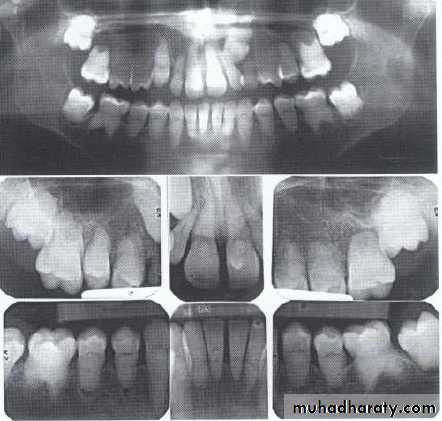

Dentin dysplasia, type I. panoramic & periapical films of the same case show the short and poorly developed roots, obliterated pulp chambers and root canals, and periapical inflammatory lesions.

Dentin dysplasia, type II. panoramic &periapical films of the same case show obliteration of the pulp chamber, reduction in the caliber of root canals, and pulp stones obscuring the flame-shaped pulp chambers.

Periapical inflammatory lesions are associated with some of the mandibular anterior teeth.